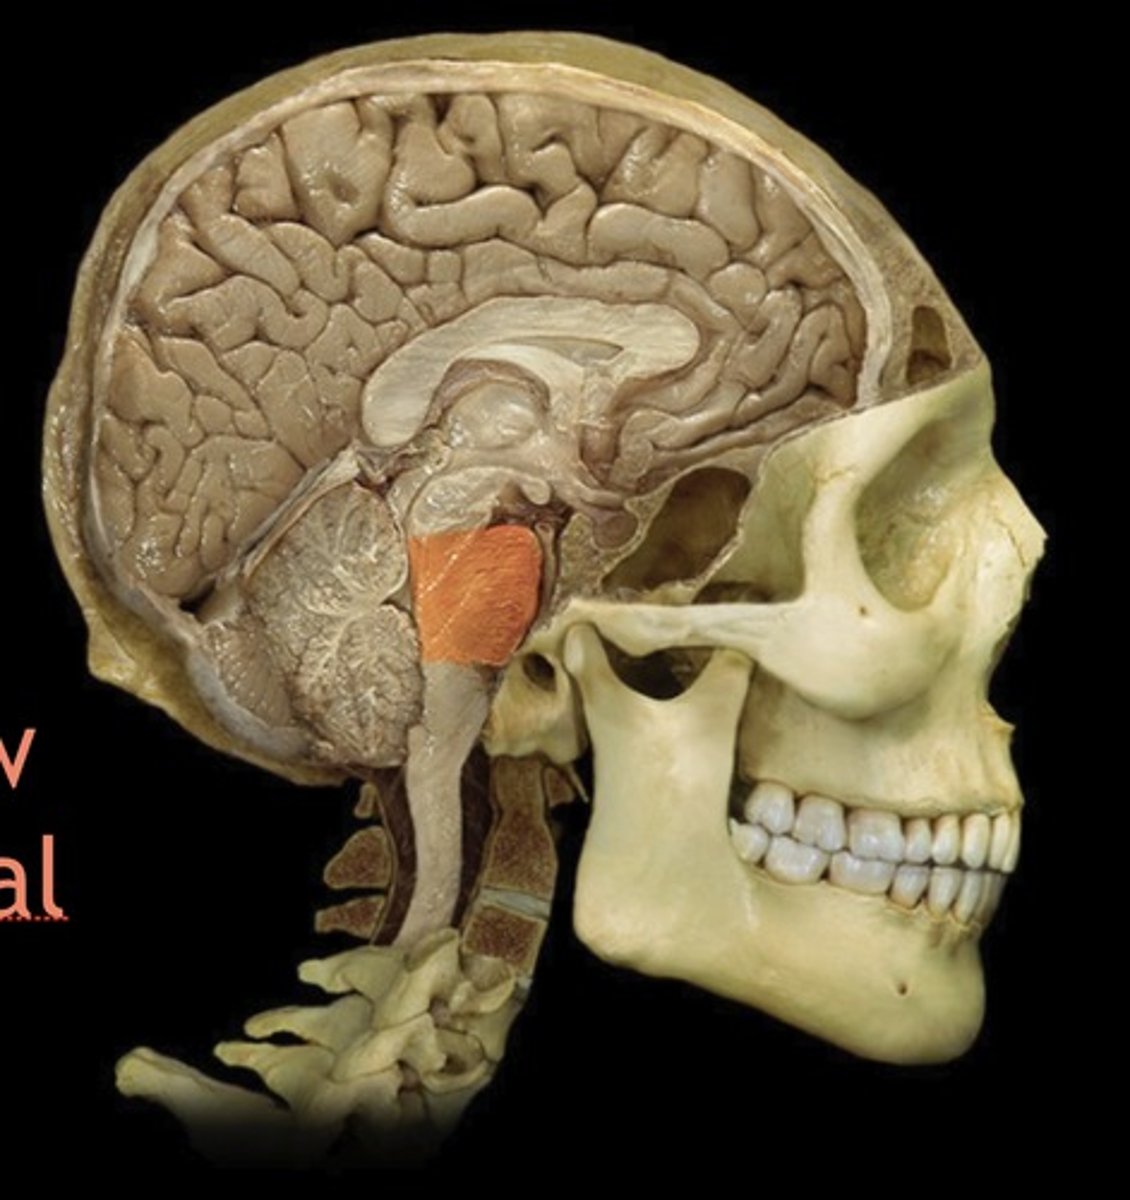

brainstem

Name this structure

Midbrain

Name this structure

Pons

Name this structure

Medulla Oblongata

Name this structure

Cerebral crus

Name this structure

Cerebral Peduncle

Name this structure

Corticospinal tract

Name this structure